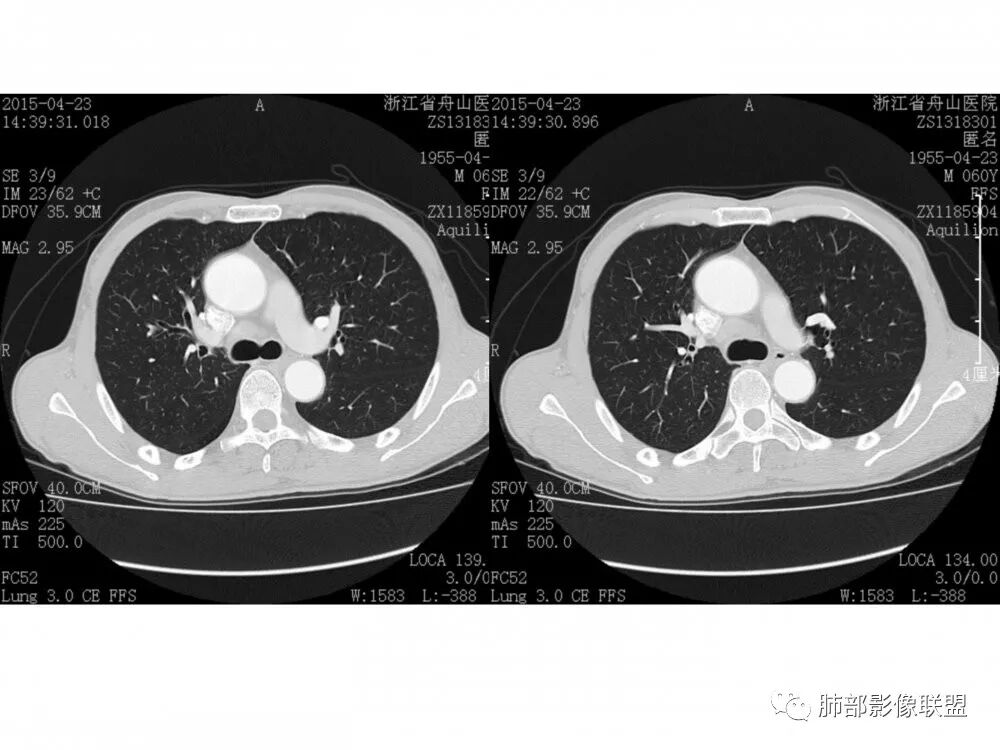

右肺下叶支气管开口新生物,轴位管腔及纵向基底干大部分受累狭窄,支气管管壁破坏明显,强化较低不均匀,肺门、7组、4R淋巴结肿大,考虑恶性支气管腔内肿瘤,鳞癌可能性大,需要与类癌、涎腺类肿瘤鉴别

老年男性,60岁,右下肺门肿块,右下支气管粘膜下生长,并堵塞,无明显阻塞性肺炎和肺不张,早期多发淋巴结转移,似不均匀强化。综合看恶性程度高,考虑大细胞癌,一个不支持点,大细胞癌外周多见。

男,60岁,右肺下叶支气管开口新生物,轴位管腔及纵向基底干大部分受累狭窄,支气管管壁破坏并突破形成腔外肿块,强化较低不均匀,右肺门、7组、4R淋巴结肿大,考虑恶性没问题,鳞癌可能性大,类癌、粘液表皮样癌,乳头状瘤待排。

右肺下叶支气管不规则软组织肿块,病灶沿支气管生长,有一定的张力,部分包绕支气管壁,增强病灶内可见中度强化,内部有延迟强化的特点,周围淋巴结增大,诊断恶性病变无疑,远端无明显支气管阻塞,主要考虑粘液表皮癌,腺样囊腺癌,鳞癌之间鉴别,病灶有类似神经源性病变生长方式,腺样囊腺癌,其次考虑鳞癌或粘液表皮癌。

病理结果:鳞癌